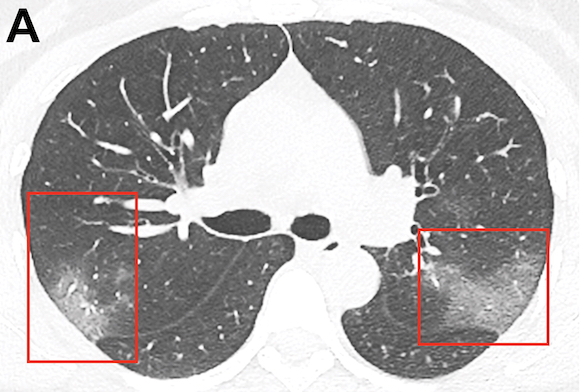

Pour chacun des 21 patients, le scanner a été évalué pour la présence d'opacités en verre dépoli ou de consolidation, le nombre de lobes affectés par ces opacités en verre dépoli ou consolidation, le degré d'implication du lobe en plus du score de gravité pulmonaire, la présence de nodules, d'un épanchement pleural, d'une lymphadénopathie thoracique et d'une maladie pulmonaire sous-jacente telle que l'emphysème ou la fibrose. Toute autre anomalie thoracique a également été notée. L'analyse a montré que le 2019-nCoV se manifeste généralement sur la TDM avec un verre dépoli bilatéral et des opacités pulmonaires consolidantes. Les opacités nodulaires et une distribution périphérique de la maladie peuvent être des caractéristiques supplémentaires utiles au diagnostic précoce. Les chercheurs ont également noté que la cavitation pulmonaire, les nodules pulmonaires discrets, les épanchements pleuraux et la lymphadénopathie sont généralement absents dans les cas de 2019-nCoV.

L'imagerie de suivi chez sept des huit patients a montré une progression légère ou modérée de la maladie, se manifestant par l'augmentation de l'étendue et de la densité des opacités de l'espace aérien. Le Dr Chung a averti que l'absence de résultats CT anormaux lors de l'examen initial n'exclut pas la présence de 2019-nCoV. « Notre population de patients est unique par rapport aux autres séries publiées sur le coronavirus de Wuhan, a-t-il précisé. Trois de nos patients ont en effet fait l’objet de TDM thoraciques initiales normales. L'un de ces patients a réagi trois jours plus tard et a développé une lésion nodulaire en verre dépoli solitaire dans le lobe inférieur droit, indiquant que ce schéma peut représenter la toute première manifestation radiologiquement visible de la maladie chez certains patients infectés par le coronavirus de Wuhan. »